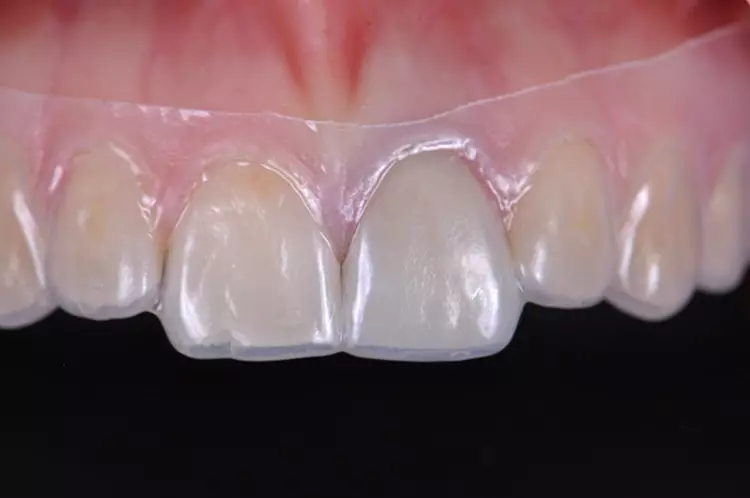

Auf den vorab hergestellten Situationsmodellen wurde für die provisorische Versorgung eine Tiefziehfolie für den Oberkiefer hergestellt. Es erfolgte die schonende Abnahme der Einzelzahnrestauration und die Entfernung des Befestigungsmaterials.

Die Gingiva wurde mithilfe eines Retraktionsfadens vorsichtig verdrängt und die zirkuläre Präparation mit einer ausgeprägten Hohlkehle klar definiert. Beim Langzeitprovisorium, welches man in der Praxis herstellte, wurden sämtliche ästhetischen und funktionellen Parameter berücksichtigt und die „äußere Hülle“ der definitiven Krone festgelegt.